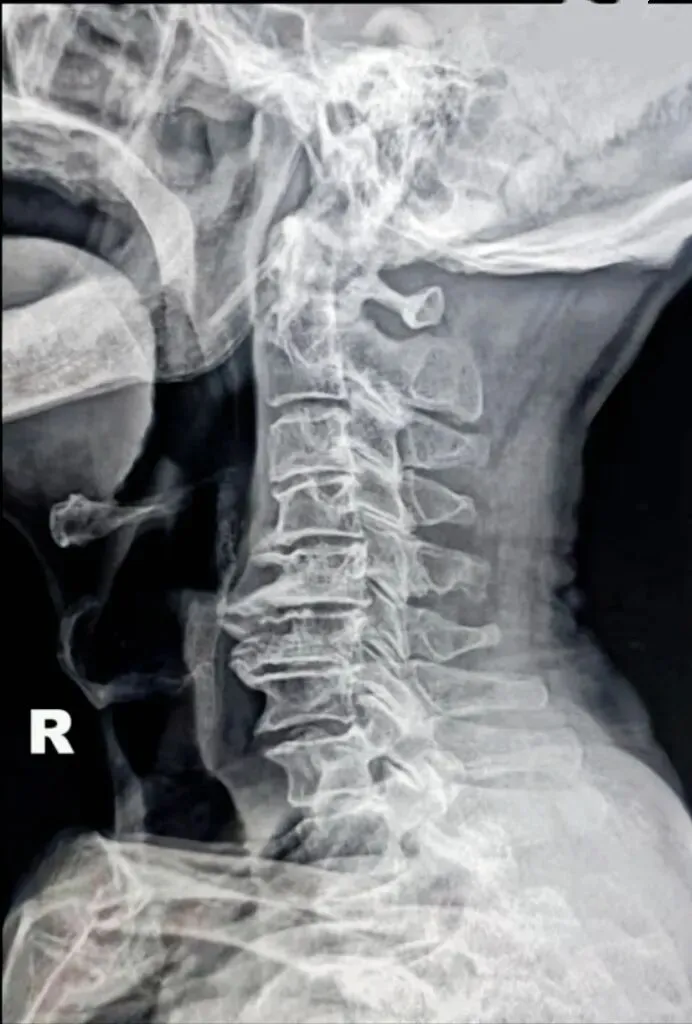

二弓指的是颈椎生理曲度,在颈椎侧位X线片中,正常生理状态下呈现向前凸出的弧形曲线,呈半C型前凸类似弓形,是人体脊柱生理曲度的重要组成部分。颈椎曲度变化能够反映颈椎整体功能的变化。

常见的颈椎曲度改变有曲度变直和曲度反曲。

颈椎生理曲度测量的方法多种多样,其中应用最广泛的测量方法是Borden法。从齿状突后上缘开始向下将每个椎体后缘相连成为一条弧线,然后从齿状突后上缘至C7椎体后下缘作一直线测量,两条线间最宽处的垂直横交线的距离即为颈椎生理曲度深度。

正常时,最宽处在C4椎体水平正常为12毫米,正负5毫米,小于7毫米为生理曲度变直,大于17毫米为生理曲度过度前屈,小于零时为生理曲度反曲。